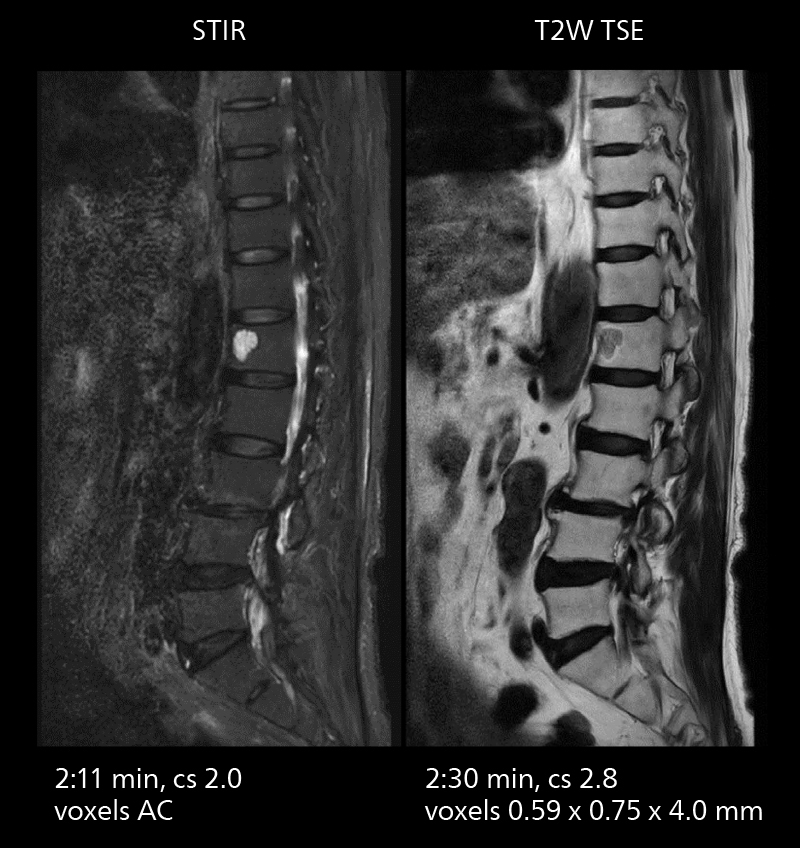

Lumbar spine MRI

Crisp images are obtained with high resolution and short scan times using Elition X. A cyst can be seen.

Lumbar spine MRI

Crisp images are obtained with high resolution and short scan times using Elition X. A cyst can be seen.